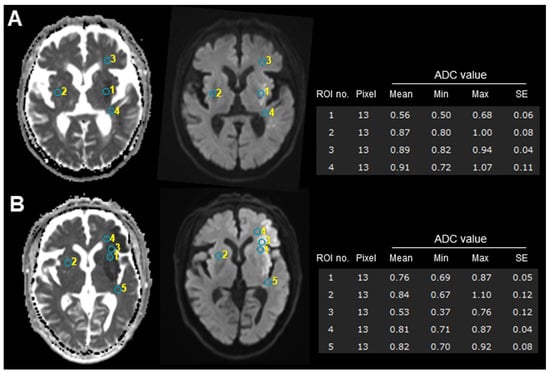

| ADC value, mean (SD) | 0.59 (0.11) | 0.52 (0.08) | 0.62 (0.10) | 0.006 * |